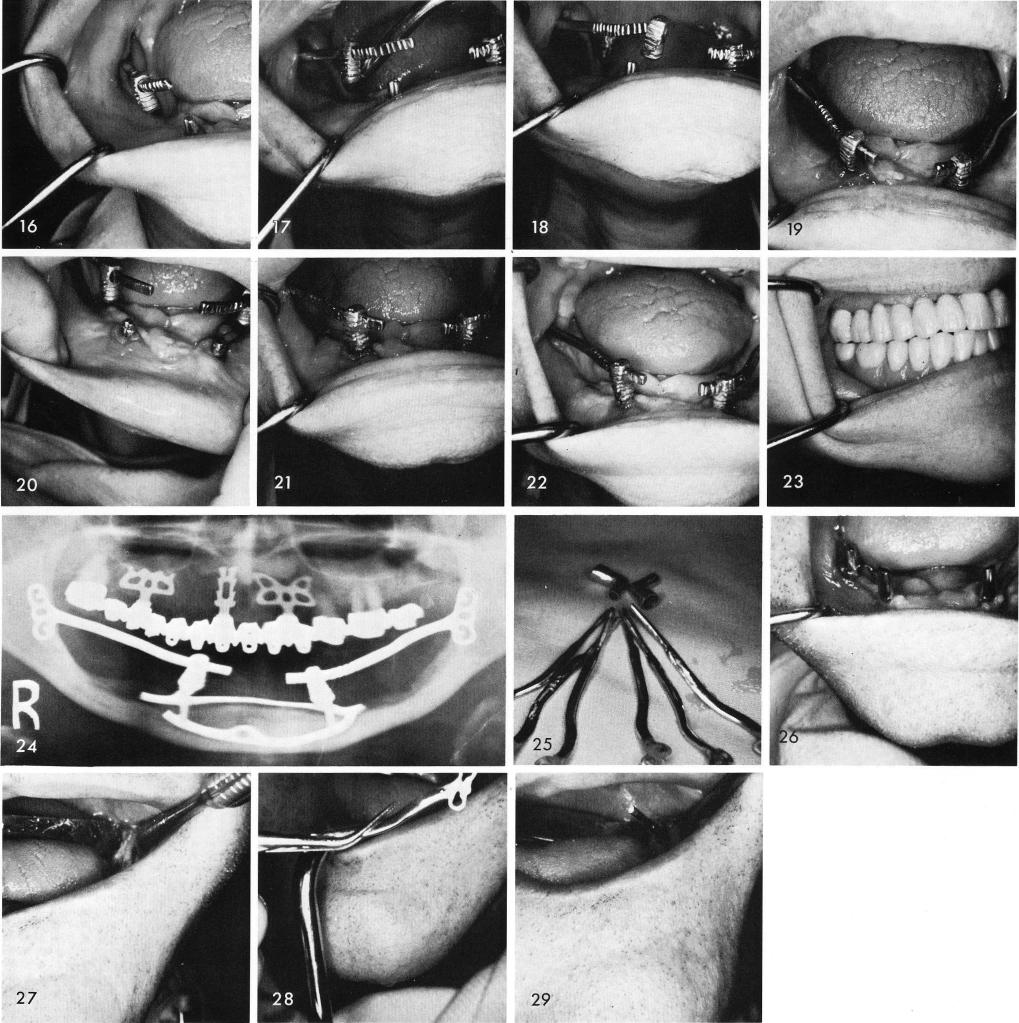

16, 17, 18, 19. They were then tapped upward for cementation, figs. 20, 21, and the posterior tissues were sutured. Healing was excellent, fig. 22, and the full denture was completed and x-rayed, figs. 23, 24. Fig. 25 shows the anterior copings with the horizontal tube extensions that must be prefabricated prior to inserting the ramus implants. Upon clinical observation the left posterior quadrant of the subperiosteal implant was previously removed, fig. 26. The tissues in the left ramus were incised and reflected to expose the bone for making of the ramus groove, fig. 27, and the implant was tapped into correct position, figs. 28, 29. The hollow tube was inserted over the

1 Prefabricated mandibular anterior copings & horizontal tube extensions